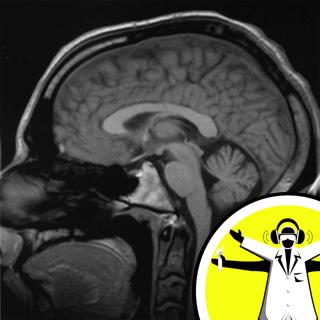

In a special show from Cambridge and New Zealand, Hannah Critchlow investigates the research into Huntington's Disease. How has the search to correct a single gene enhanced our understanding of how the brain functions? How are sheep helping to unpick the pizzle of the human mind? Plus we visit a brain bank to find out how tissue donors are supporting the scientific research. Like this podcast? Please help us by supporting the Naked Scientists